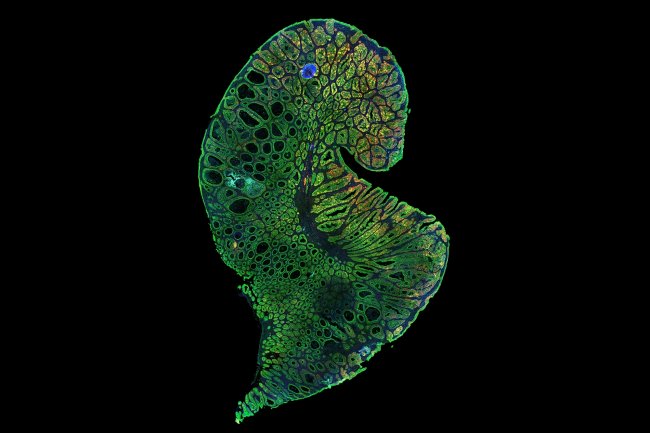

Tag : Stem cell

How does the body renew itself with stem cell

How does the body renew itself? How do cancer cells use the same or similar processes to form tumors and spread throughout the body?...

What is Stem Cell

A cell that can divide to form more stem cells as well as giving rise to specialized cells (blood cells, nerve cells, muscle cells,...